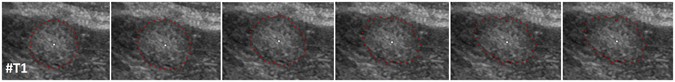

Figure 5

Segmentation results for different delta values: Δr = 0 (leftmost) to Δr = 5 (rightmost). Note, the user-defined seed point in white remains for all segmentations at the same position.